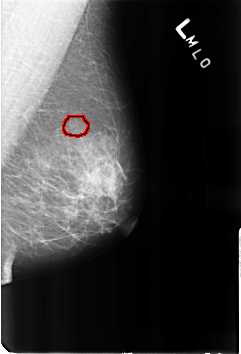

B_3215_1.LEFT_MLO

FILE: B_3215_1.LEFT_MLO.OVERLAY

TOTAL_ABNORMALITIES 1

ABNORMALITY 1

LESION_TYPE CALCIFICATION TYPE PUNCTATE DISTRIBUTION SEGMENTAL

ASSESSMENT 2

SUBTLETY 3

PATHOLOGY BENIGN_WITHOUT_CALLBACK

TOTAL_OUTLINES 1

BOUNDARY